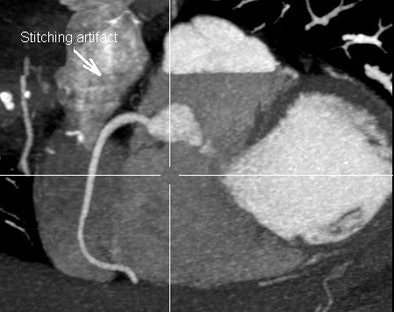

![]() |

| Coronary CT angiography and triple-rule-out results, 320- versus 64-detector-row CT. Table courtesy of Dr. Melissa Daubert. |